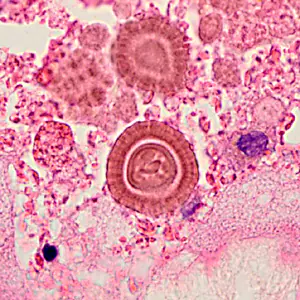

A 26-year-old female presented at a local hospital with severe pain and bloody discharge from the ear. The symptoms started while on a returning flight from vacation in Central America. The patient explained that while on vacation she visited a local physician to have a fly removed from her ear canal.